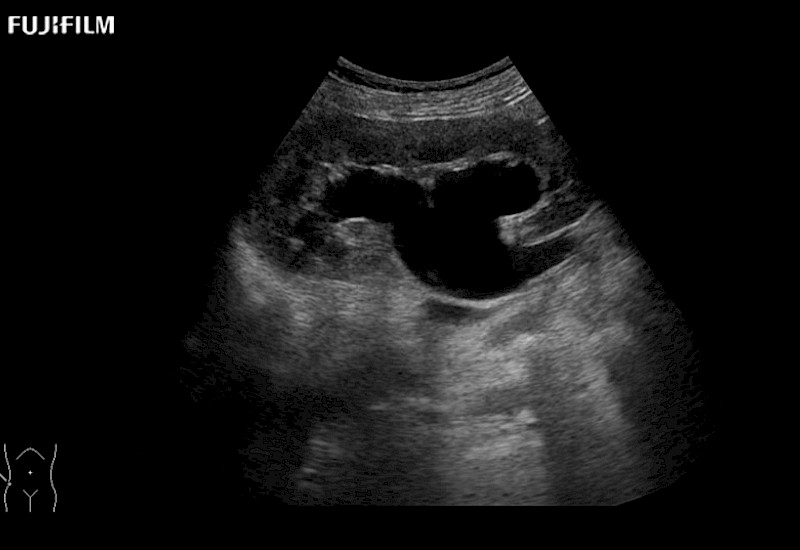

Exclusive linear array robotic surgery transducer.

Downloads:

Robot-Assisted Partial Nephrectomy Brochure (.pdf)

Features:

Main Specifications: